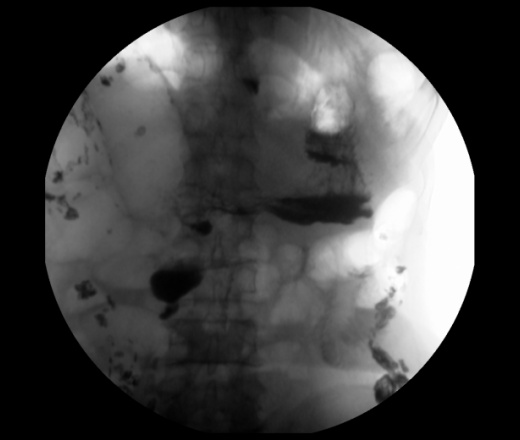

Мужчина 73 года. Жалобы на сниженный аппетит, слабость. Исследование выполенено через несколько дней после ирригоскопии. По результатам ЭФГДС гастрит.

Угол желудка развернут, ригиден. Стойкое циркулярное сужение антрального отдела.Перистальтики нет. Складки прослеживаются.

Эндофитный C-r антрального отдела.